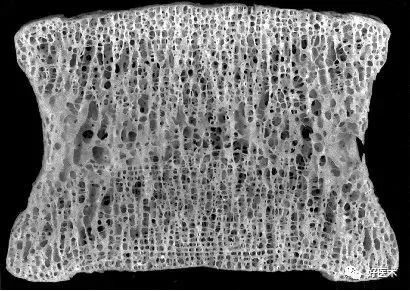

骨质疏松是以骨量减少和骨组织显微结构退行性改变为特征,骨质脆性增加,易发骨折的全身代谢性骨病。

正常

骨质疏松

严重骨质疏松

骨质疏松症的特点

全身骨量减少 骨组织显微结构退行性改变(破渔网) 骨脆性增加,轻中度外力作用下发生骨折 腰背疼痛、驼背、身长缩短、骨折 生化改变:性激素、VitD代谢产物水平降低、肠钙吸收降低2.2 骨质疏松症的病因分类

原发性骨质疏松--骨组织退变

钙逐渐丢失 骨密度下降 松质骨骨小梁变细、断裂 皮质骨板层结构紊乱、多孔原发性骨质疏松分型

甲状旁腺素 降钙素 性激素 维生素D骨质疏松症的骨形态学计量诊断

活体骨组织制成切片,显微镜下观察 测定骨小梁面积和周径、类骨质宽度 用于疑难病例的鉴别诊断及骨代谢研究4.3骨质疏松症的诊断标准